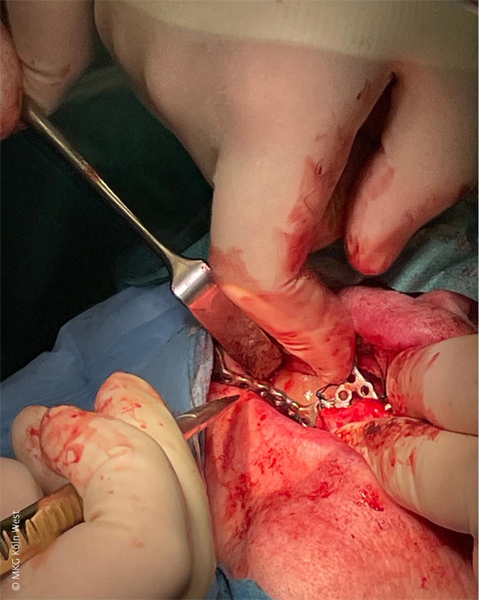

Anschließend wurde das einteilige Titan-Implantatgerüst inseriert und mit 1,5 mm-Titanschrauben (KLS Martin) an insgesamt vier Fixationspunkten stabil am Oberkiefer verschraubt (unter anderem paramaxillär und im Jochbeinbereich). Zur Austrittssicherung der vier Implantatpfeiler durch die Schleimhaut wurden gezielt kleine Stichinzisionen in der fixierten Gingiva angelegt.

Vor Wundverschluss erfolgte zur Optimierung der Weichgewebslager ein Bichat-Fettkörper-Verschiebelappen beidseits zur zusätzlichen Polsterung des Implantats (vestibuläre Abdeckung der Gerüstanteile). Die spannungsfreie mehrschichtige Wundadaptation konnte im Anschluss erreicht werden.